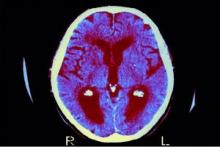

این مطالعه نشان داد که سطح بالاتر سرب خون بین سنین ۴ تا ۶ سال، حتی در سطوح نسبتاً پایین مواجهه، به طور قابل توجهی با سرعت بیشتر فراموشی مرتبط است، به طوری که میانگین سطح سرب خون تقریباً ۱.۷ میکروگرم در دسیلیتر است.

این یافتهها نشان میدهد که حتی مواجهه با سرب در سطوح پایین نیز میتواند عملکردهای شناختی حیاتی را در اوایل کودکی به خطر بیندازد.